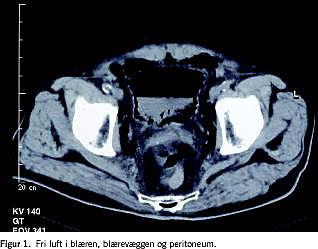

En 74-årig mand, der ikke tidligere havde været hospitaliseret, men havde haft type 2-diabetes, kronisk obstruktiv lungesygdom og forhøjet blodtryk gennem mange år, blev indlagt akut efter to uger varende, tiltagende abdominalsmerter. Patienten var metabolisk acidotisk, havde svært forhøjede infektionsparametre, samt blodsukker (B-glukose) på 20 mmol/l. Objektivt fandt man abdomen spændt, diffust ømt og med peritoneal reaktion. En akut computertomografi viste fri luft i blæren, blærevæggen og i peritoneum (Figur 1).